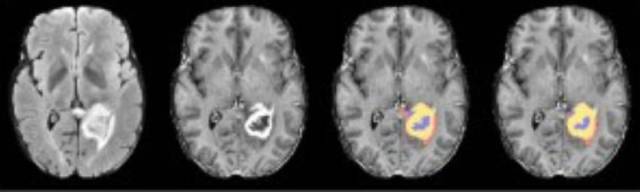

机器自动标记脑出血区域

去医院看病不可避免的一件事情就是“拍片”,不同的科室、不同的检验方法会产生各种各样的医学片子,X光、CT、核磁、病理、B超、OCT、超声等等,这些片子必须由放射科或病理科的专业医师进行解读,患者往往要等上好几个小时才能拿到解析报告,而且准确度和医生的经验有很大的相关性。一个不争的事实是,我国医学影像误诊人数每年达到5700万,主要发生在基层医疗机构。我国医学影像数据量每年增长30%,而专业医师的增长率仅仅只有4.1%,巨大的缺口催生了急迫的需求。据调查,AI可将医生的看片时间平均减少4.25个小时,准确率提高到90%以上。